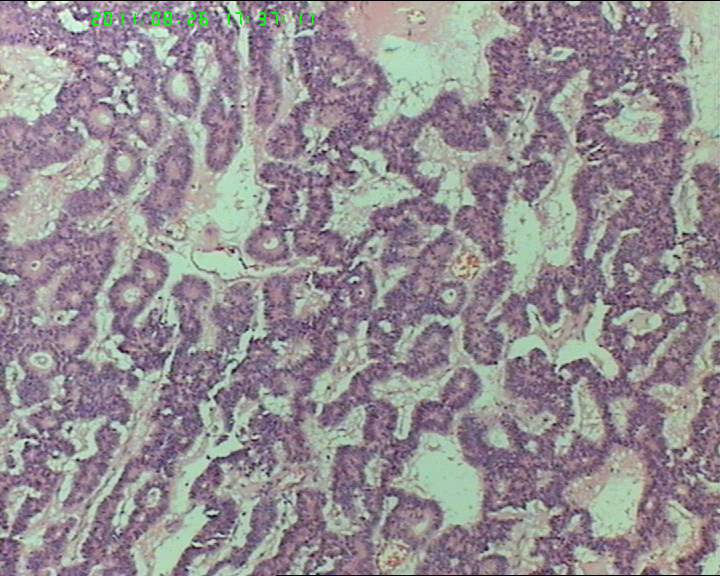

76岁女性卵巢巨大囊性肿物

卵巢肿物,大小18*14*10cm

,切面灰黄色,中央见一囊腔,12*4cm大小,未见内容物,内壁光滑。囊壁厚约4cm。